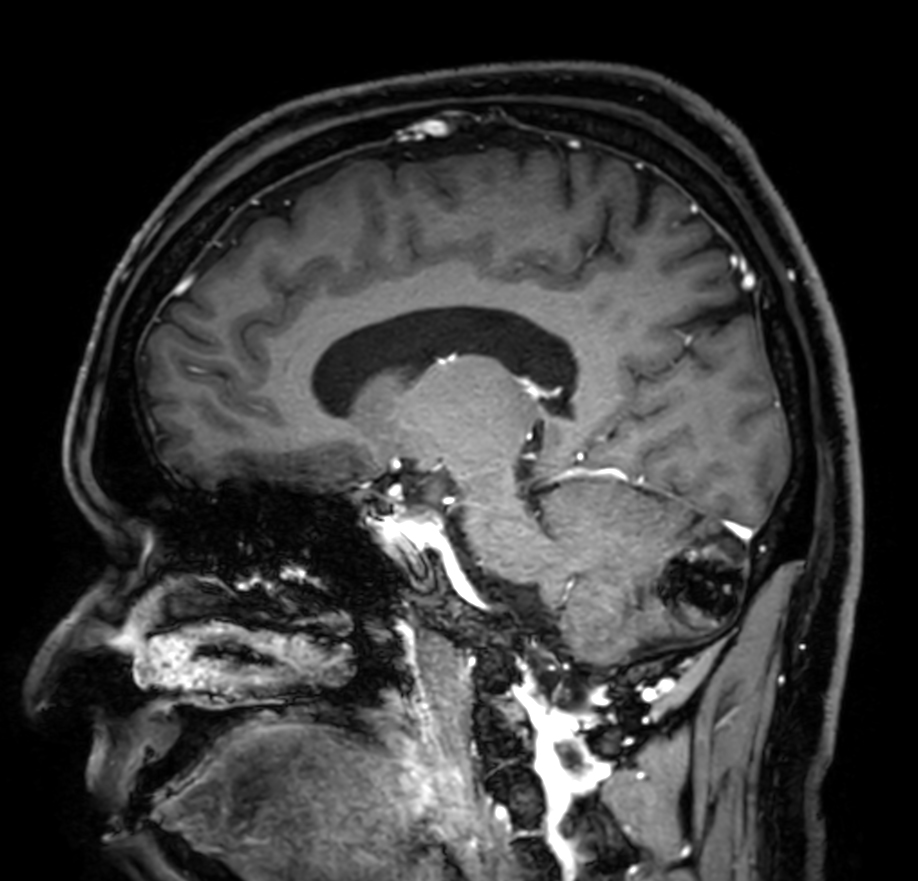

Patient with a lesion in the cerebellum. The ExamCard includes Compressed SENSE to accelerate the entire exam and techniques for motion reduced imaging (MultiVane XD), 3D imaging to acquire high resolution data in multiple directions, 3D susceptibility weighted imaging (SWIp), angiography sequences (Time-of-Flight and Contrast-Enhanced MRA with both arterial and venous phases), DTI with MultiBand SENSE to acquire a high number of diffusion directions in a short scan time and EPIC Brain to bring down any residual distortion.

T1w FFE post-gado Compressed SENSE